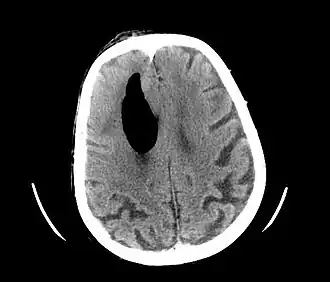

Pneumocéphale secondaire à une lésion neurochirurgicale

Le pneumocéphale, appelé aussi pneumocéphalie ou pneumencéphalie, correspond à la présence de gaz dans ou autour de l'encéphale à la suite d'une brèche ostéo-méningée.